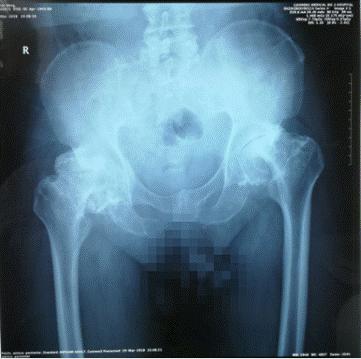

据患者回忆,双侧下肢疼痛始于2001年初的一次外伤,从树上掉下后出现双侧膝关节疼痛,不久双侧髋关节出现疼痛,进行性加重。在经历了18年病痛折磨后,患者来到门诊,此时双侧髋关节已经严重僵硬,步履维艰。右侧髋关节仅能屈曲10°,左侧髋关节屈曲活动40°,后伸、内收、外展、内旋、外旋均为0°。X线影像显示双侧髋关节重度骨性关节炎,关节周围大量骨赘形成,闭孔血管附近被大量骨赘占据。

术前髋关节X线片